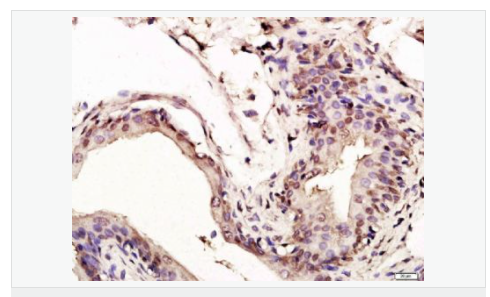

| 產(chǎn)品應(yīng)用 | WB=1:1000-2000 ELISA=1:1000-5000 IHC-P=1:100-500 IHC-F=1:100-500 Flow-Cyt=1ug/Test ICC=1:100-500 IF=1:100-500 (石蠟切片需做抗原修復(fù)) not yet tested in other applications. optimal dilutions/concentrations should be determined by the end user. |

| 細(xì)胞定位 | 細(xì)胞核 細(xì)胞漿 |